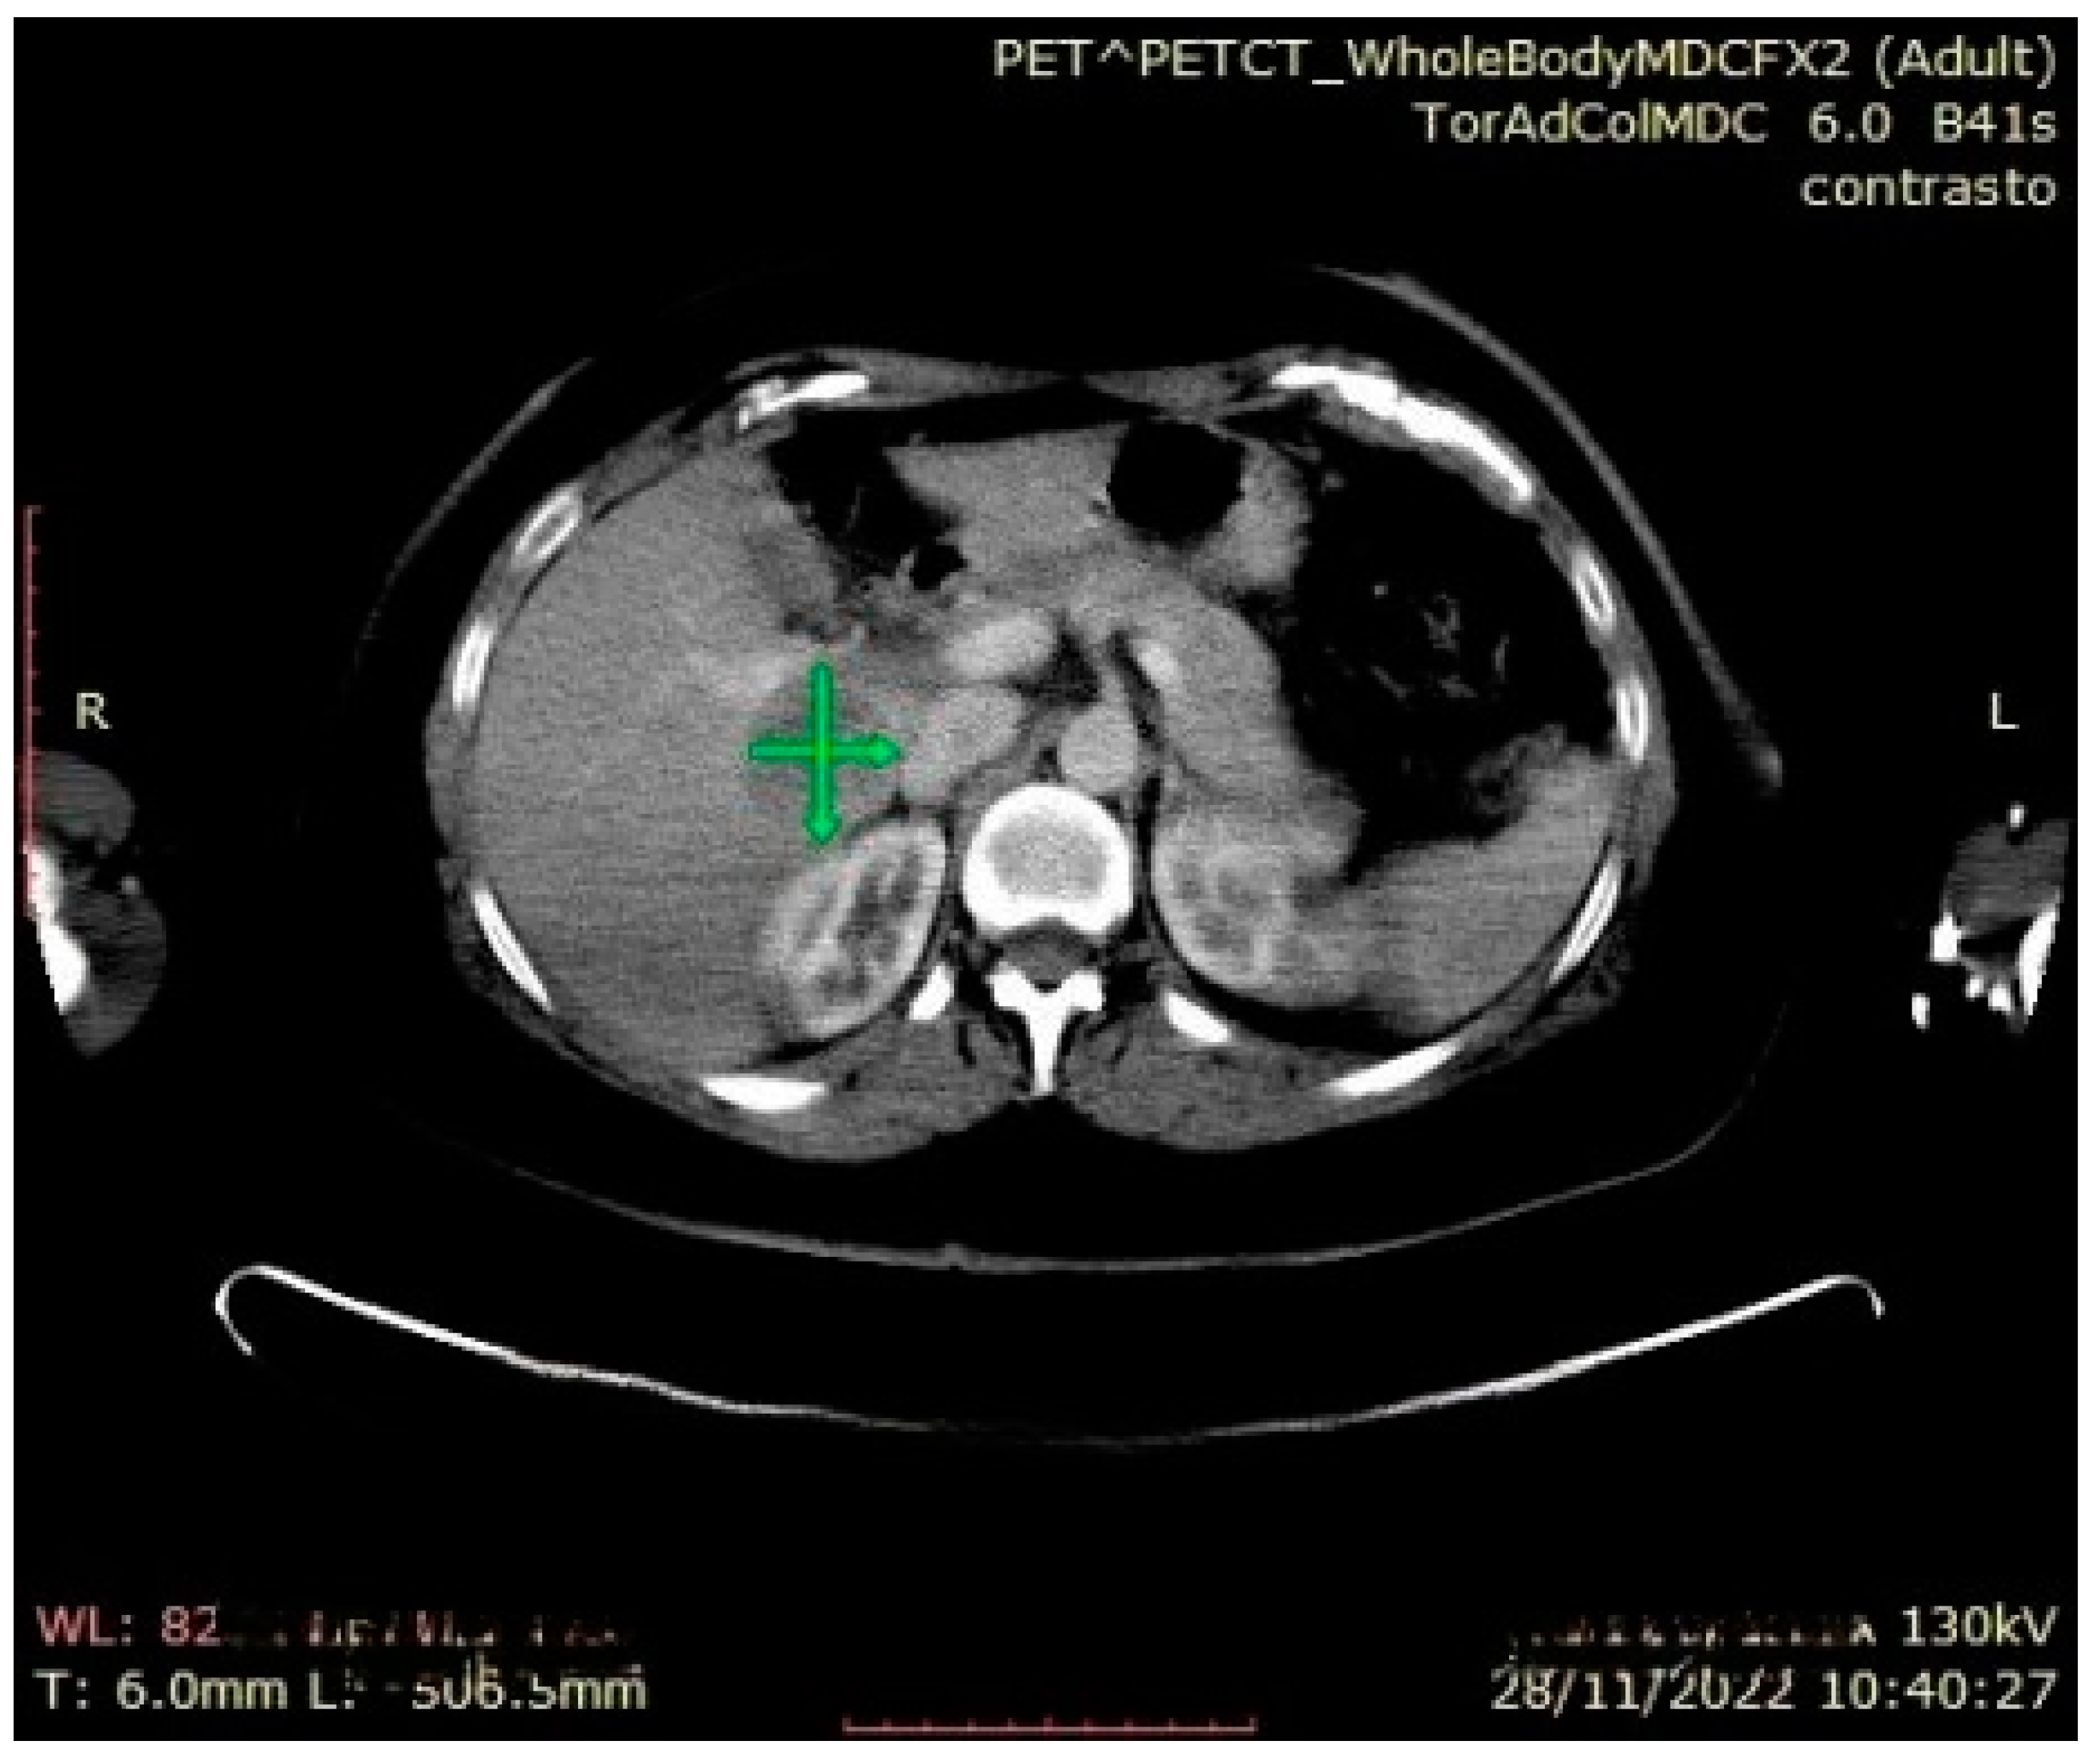

During the follow-up examination at 4 months post-surgery, a PET-CT scan without contrast conducted at another facility revealed a prominent focal hypermetabolic lesion in the hepatic segment V measuring approximately 51 × 44 mm with a SUV of 14.3, indicative of a secondary lesion. Additionally, osteolytic lesions were observed along the lateral aspect of the third rib on the right hemithorax (SUV max 3.5) and the inferior angle of the left scapula (SUV max 3.2), along with multiple bilateral pulmonary nodules (SUV max 1.2) [Figure 5, Figure 6 and Figure 7]. Hence, the aggressive metastatic dissemination of leiomyosarcoma underscores the imperative for a prompt reassessment of the treatment approach and the contemplation of intensified therapeutic interventions.

Figure 7.

Abdominal CT: hepatic metastasis identified with green arrows.